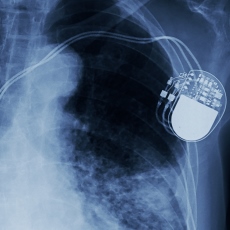

An arrhythmia is any disorder of your heart rate or rhythm. It means that your heart beats too quickly, too slowly, or with an irregular pattern. Most arrhythmias result from problems in the electrical system of the heart. If your arrhythmia is serious, you may need a cardiac pacemaker or an implantable cardioverter defibrillator (ICD). They are devices that are implanted in your chest or abdomen.

A pacemaker helps control abnormal heart rhythms. It uses electrical pulses to prompt the heart to beat at a normal rate. It can speed up a slow heart rhythm, control a fast heart rhythm, and coordinate the chambers of the heart.

Getting a pacemaker or ICD requires minor surgery. You usually need to stay in the hospital for a day or two, so your doctor can make sure that the device is working well. You will probably be back to your normal activities within a few days.